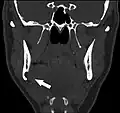

Additional images

Stafne bone cavity seen on coronal CT